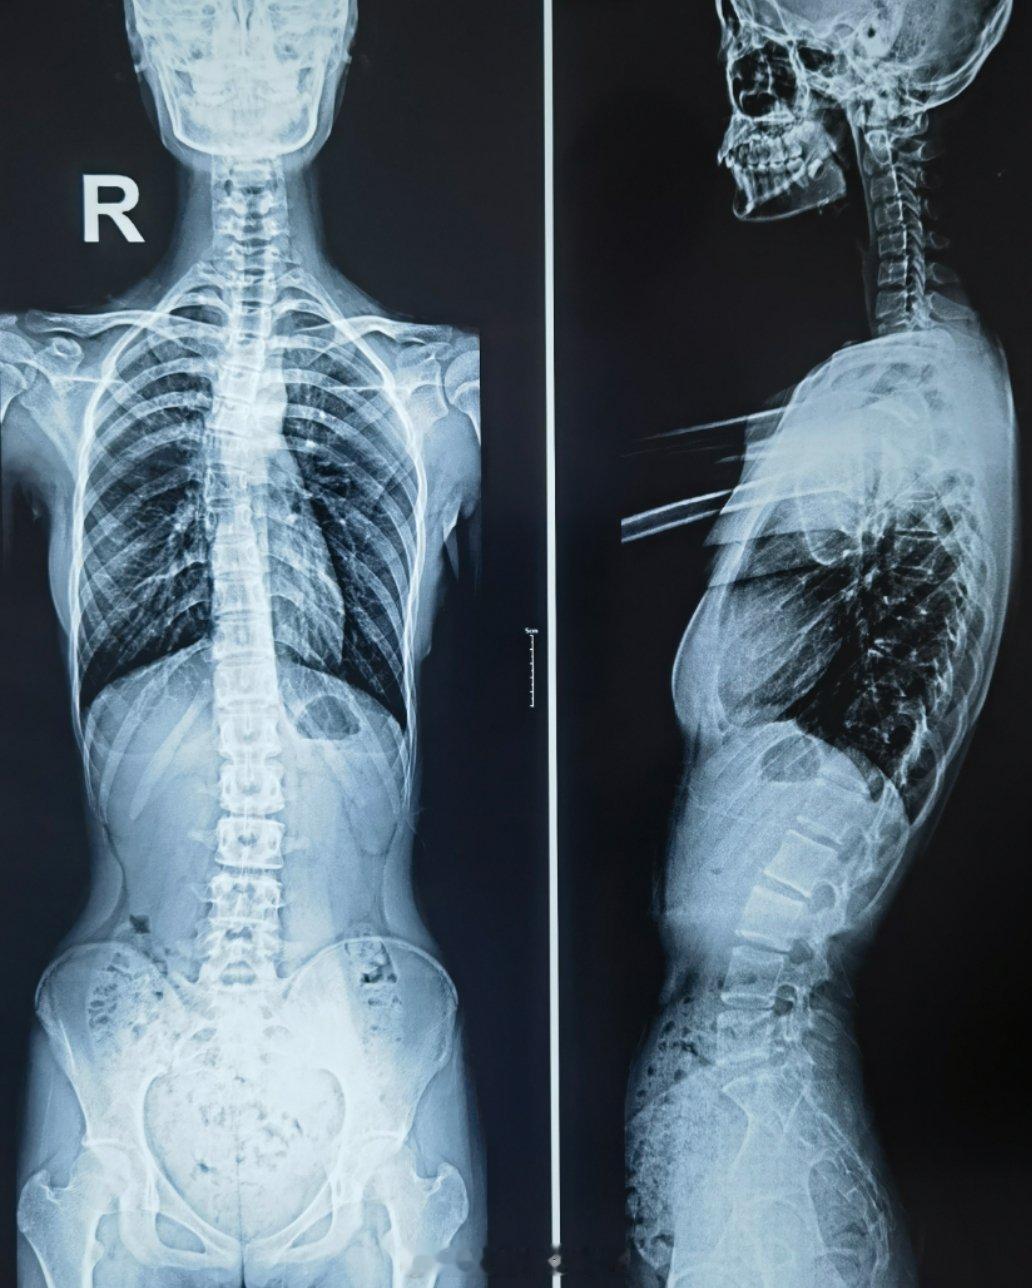

小姑娘16岁175cm,体重80斤,洗澡的时候妈妈发现双侧肩胛骨不对称来诊,拍脊